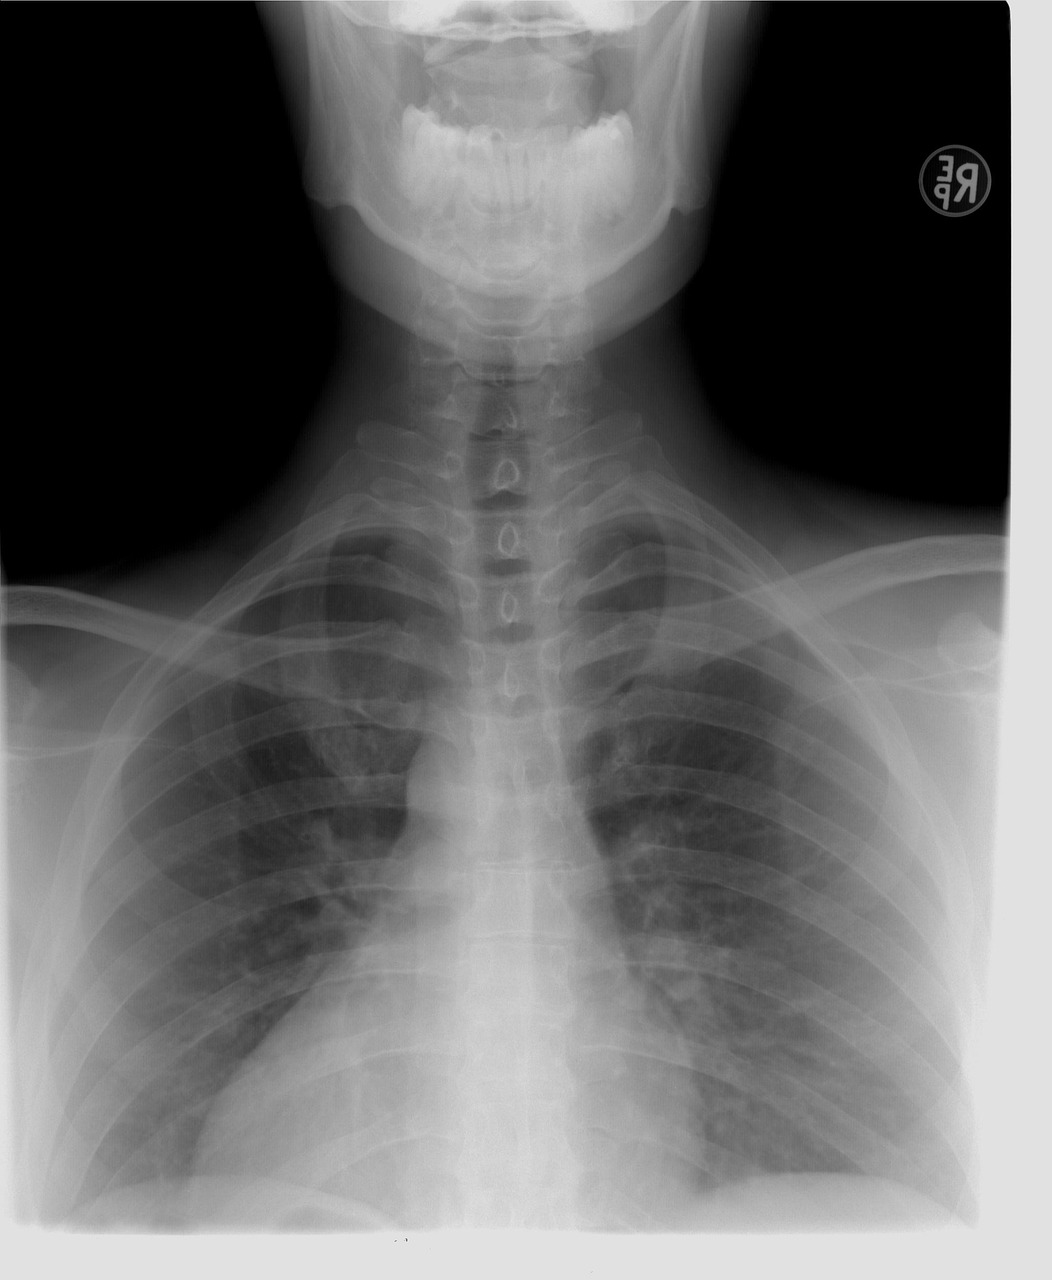

- 흉부 X-ray 촬영 : 폐 결핵, 폐렴, 폐암 등 흉부 질환의 유무를 확인합니다.